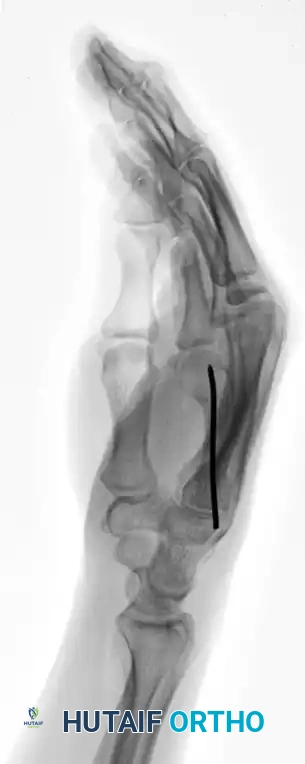

This technique is equally effective for mid-shaft fractures, as demonstrated in the fourth metacarpal example below:

FIGURE 67-37A: Preoperative AP radiograph of a fourth metacarpal shaft fracture.

FIGURE 67-37B: Preoperative lateral radiograph of the fourth metacarpal fracture.

FIGURE 67-37C: Postoperative AP radiograph showing intramedullary fixation with a Kirschner wire.

FIGURE 67-37D: Postoperative lateral radiograph confirming anatomic restoration.